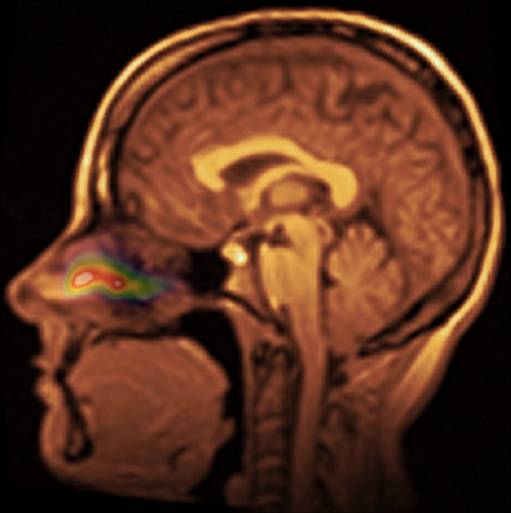

Several inhaled drug formulations were studied by radiolabeling the active ingredient (several different steriods) with C-11 or F-18, formulating that ingredient as the dosage form (different MDI, DPI, and nebulizer formulations), and performing quantitative PET studies of the regional biodistribution and kinetics.

Click on images to see additional examples, larger versions, and videos.